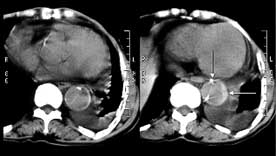

女性,71岁,胸骨后疼痛两小时来诊。体检:心界左下扩大,心率70次/每分,律齐,无杂音。x线胸片示:纵隔增宽。

ct平扫:降主动脉全程约18cm范围内管腔扩张,管腔被条索影分隔成前内、外后两腔,条索影与管壁连接处见散在点状钙化影。

增强扫描:见前内腔较小,与主动脉弓同步强化;后外腔较大,造影剂消退时间教主动脉弓延长,切管壁不均匀增厚,强化不明显。

ct诊断:降主动脉夹层动脉瘤,伴附壁血栓形成。